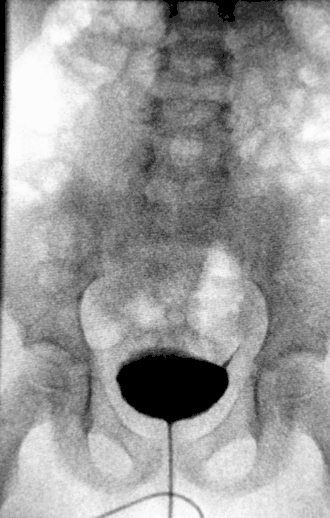

![]() Урограмма почек, пораженных гидронефрозом | |

Диагноз ставится на основании УЗИ, экскреторной урографии и ренографии.

При пренатальном диагностировании степень заболевания определяется размером почечной лоханки, замеряемым посредством УЗИ.